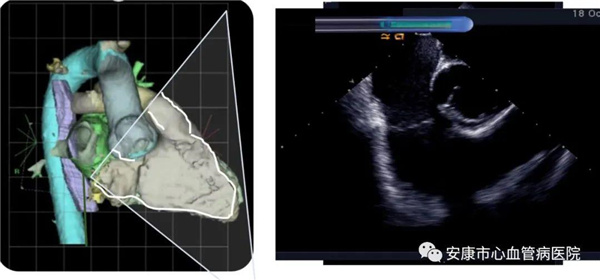

心律失常團(tuán)隊在11月6日為患者在ICE引導(dǎo)下行房撲射頻消融術(shù)。穿刺左鎖骨下靜脈,導(dǎo)絲走行證實了合并永存左上腔靜脈。穿刺右股靜脈,分別送入心腔內(nèi)超聲導(dǎo)管和消融電極,超聲下建立右心室、右心房、左心室、左心房、二尖瓣和三尖瓣及三尖瓣峽部模型。ICE就像術(shù)者多了一雙天眼,可以對心臟內(nèi)部結(jié)構(gòu)一目了然,360度無死角觀察心臟結(jié)構(gòu),可以做到“所視即所及”。建模后,消融三尖部峽部,房撲很快終止,轉(zhuǎn)為竇性心律,手術(shù)獲得成功!手術(shù)用時僅70分鐘,術(shù)后病情穩(wěn)定,安全返回病房。

心腔內(nèi)超聲(Intracardiac Echocaiography ICE)是將微型的換能器安裝在心導(dǎo)管的尖端,再經(jīng)外周血管(動脈或靜脈)送至心腔,換能器發(fā)射聲波,然后將接受到的回波經(jīng)計算機(jī)處理后形成超聲圖像。由于換能器放置在心腔內(nèi),不受空氣等因素的干擾,因此比經(jīng)食道超聲檢查圖像更加清晰,可以辨別心內(nèi)的細(xì)微結(jié)構(gòu),臨床上主要用于指導(dǎo)心律失常的射頻消融治療。

ICE不僅能檢查左心耳結(jié)構(gòu)、指導(dǎo)房間隔穿刺,而且能精確構(gòu)建左房及肺靜脈解剖結(jié)構(gòu),量化前庭部位與肺靜脈口部的距離,精準(zhǔn)的消融一些復(fù)雜心律失常病例;并且能精確構(gòu)建食道,量化食道與后壁的距離,降低食道損傷幾率;術(shù)中動態(tài)監(jiān)測積液變化,實時監(jiān)測并發(fā)癥,早發(fā)現(xiàn)早處理。因此心腔內(nèi)超聲真可謂是房顫射頻消融手術(shù)安全保障的一只“天眼”。此外這只“天眼”現(xiàn)在還應(yīng)用于心臟瓣膜手術(shù)、起搏器植入等心臟介入手術(shù)。